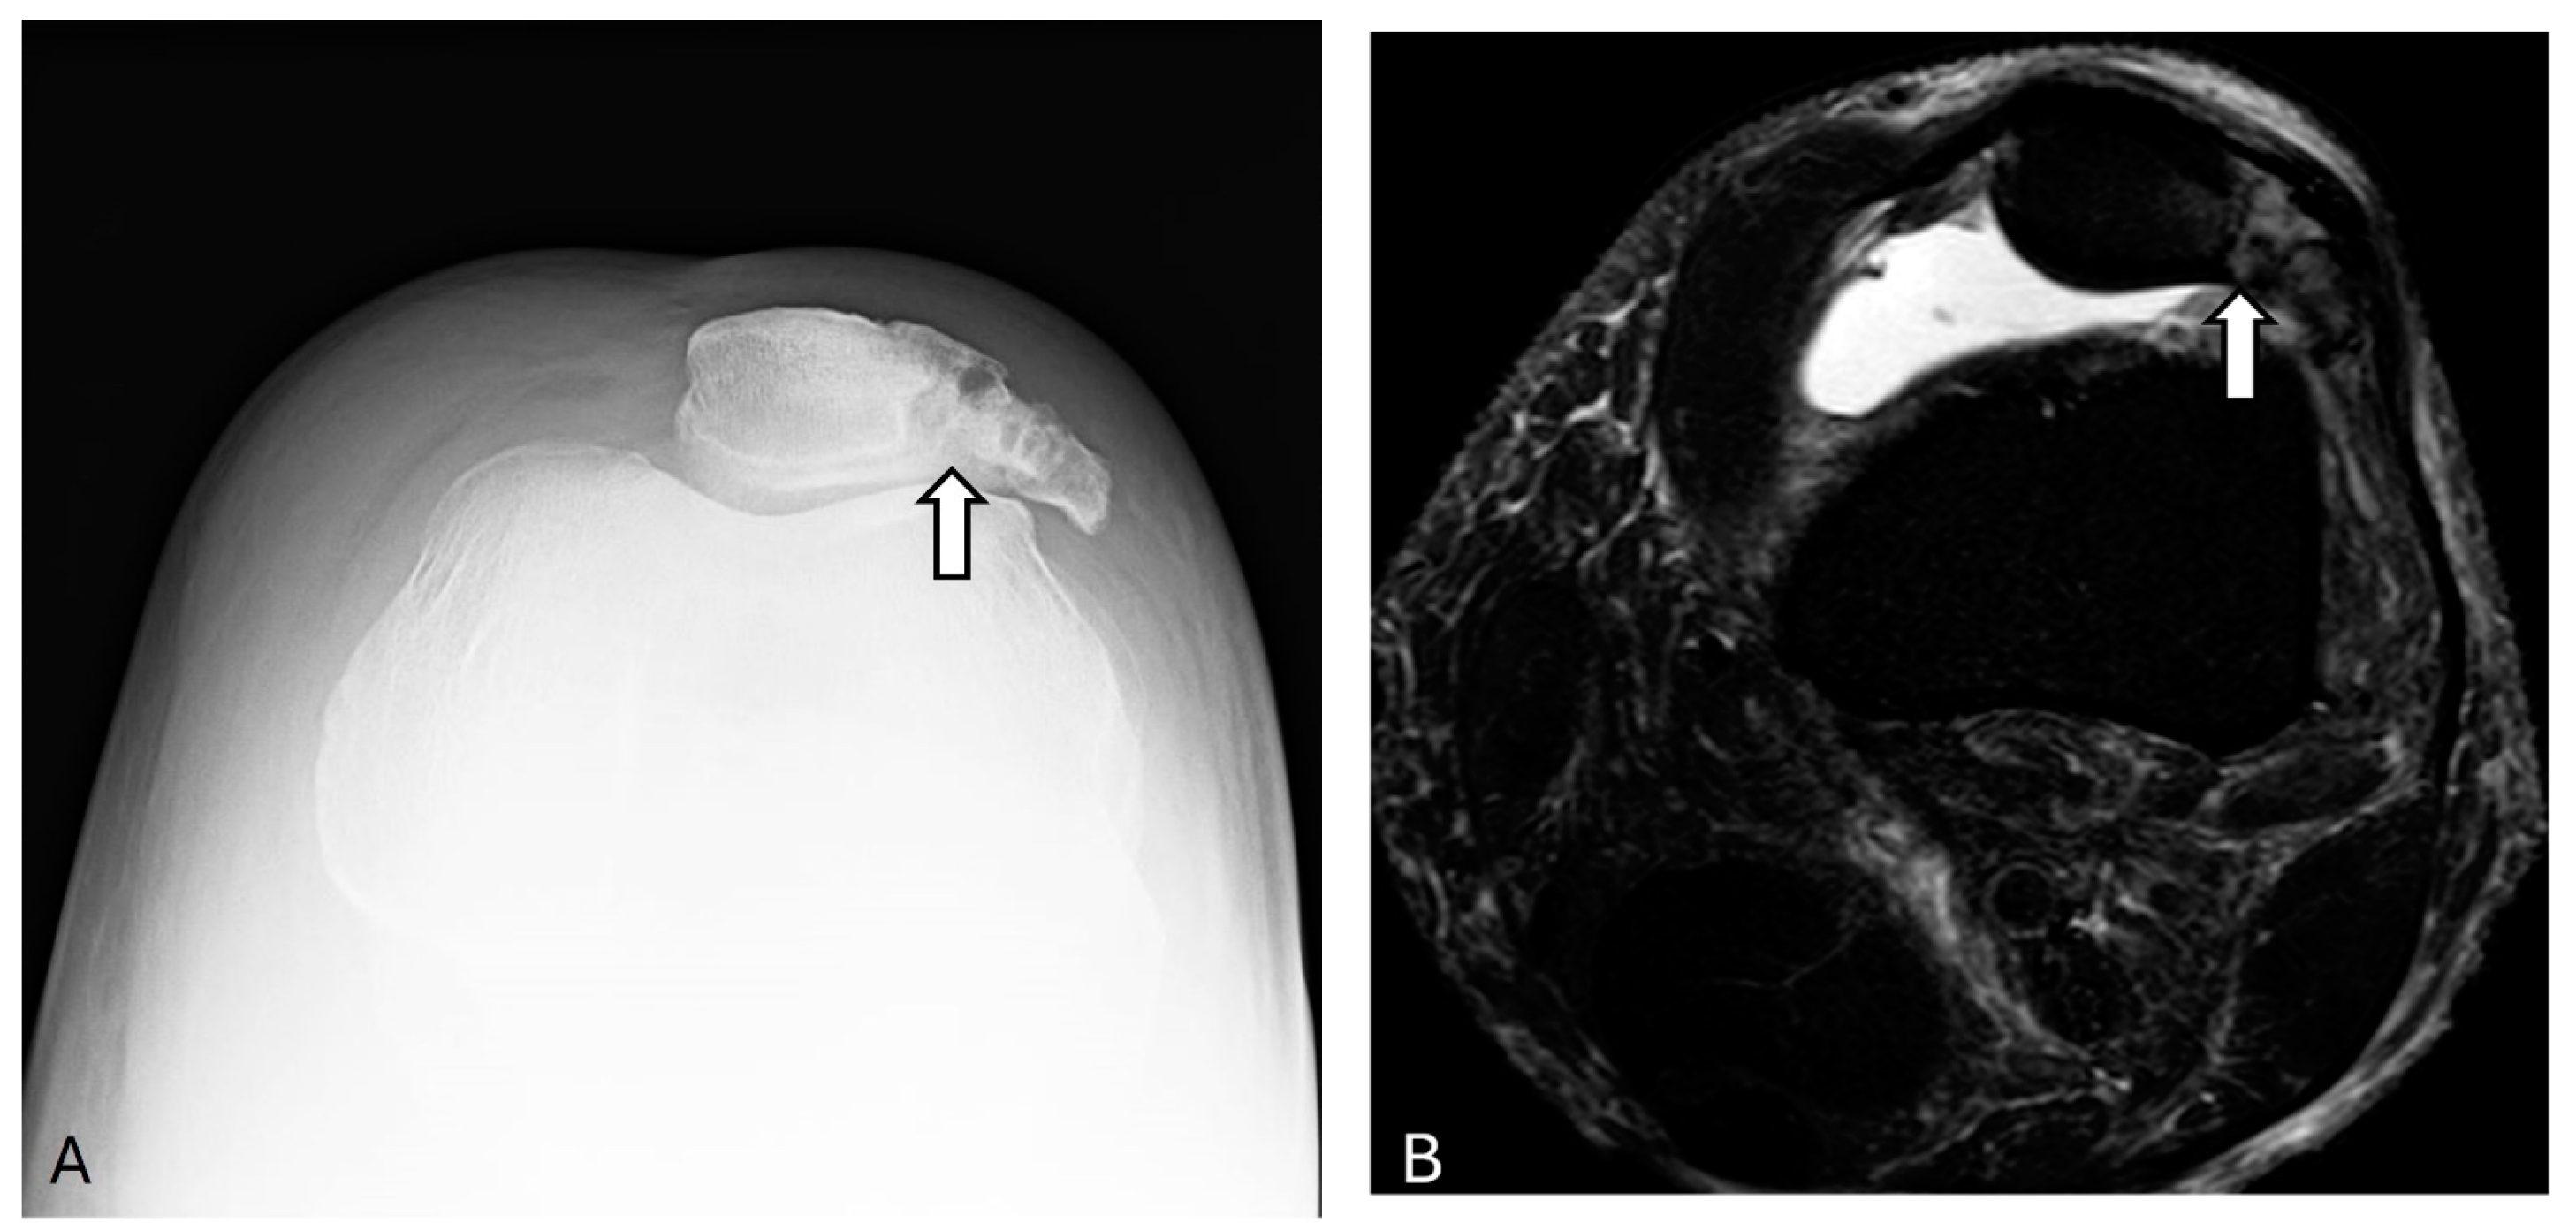

2.1. Bipartite/Multipartite Patella